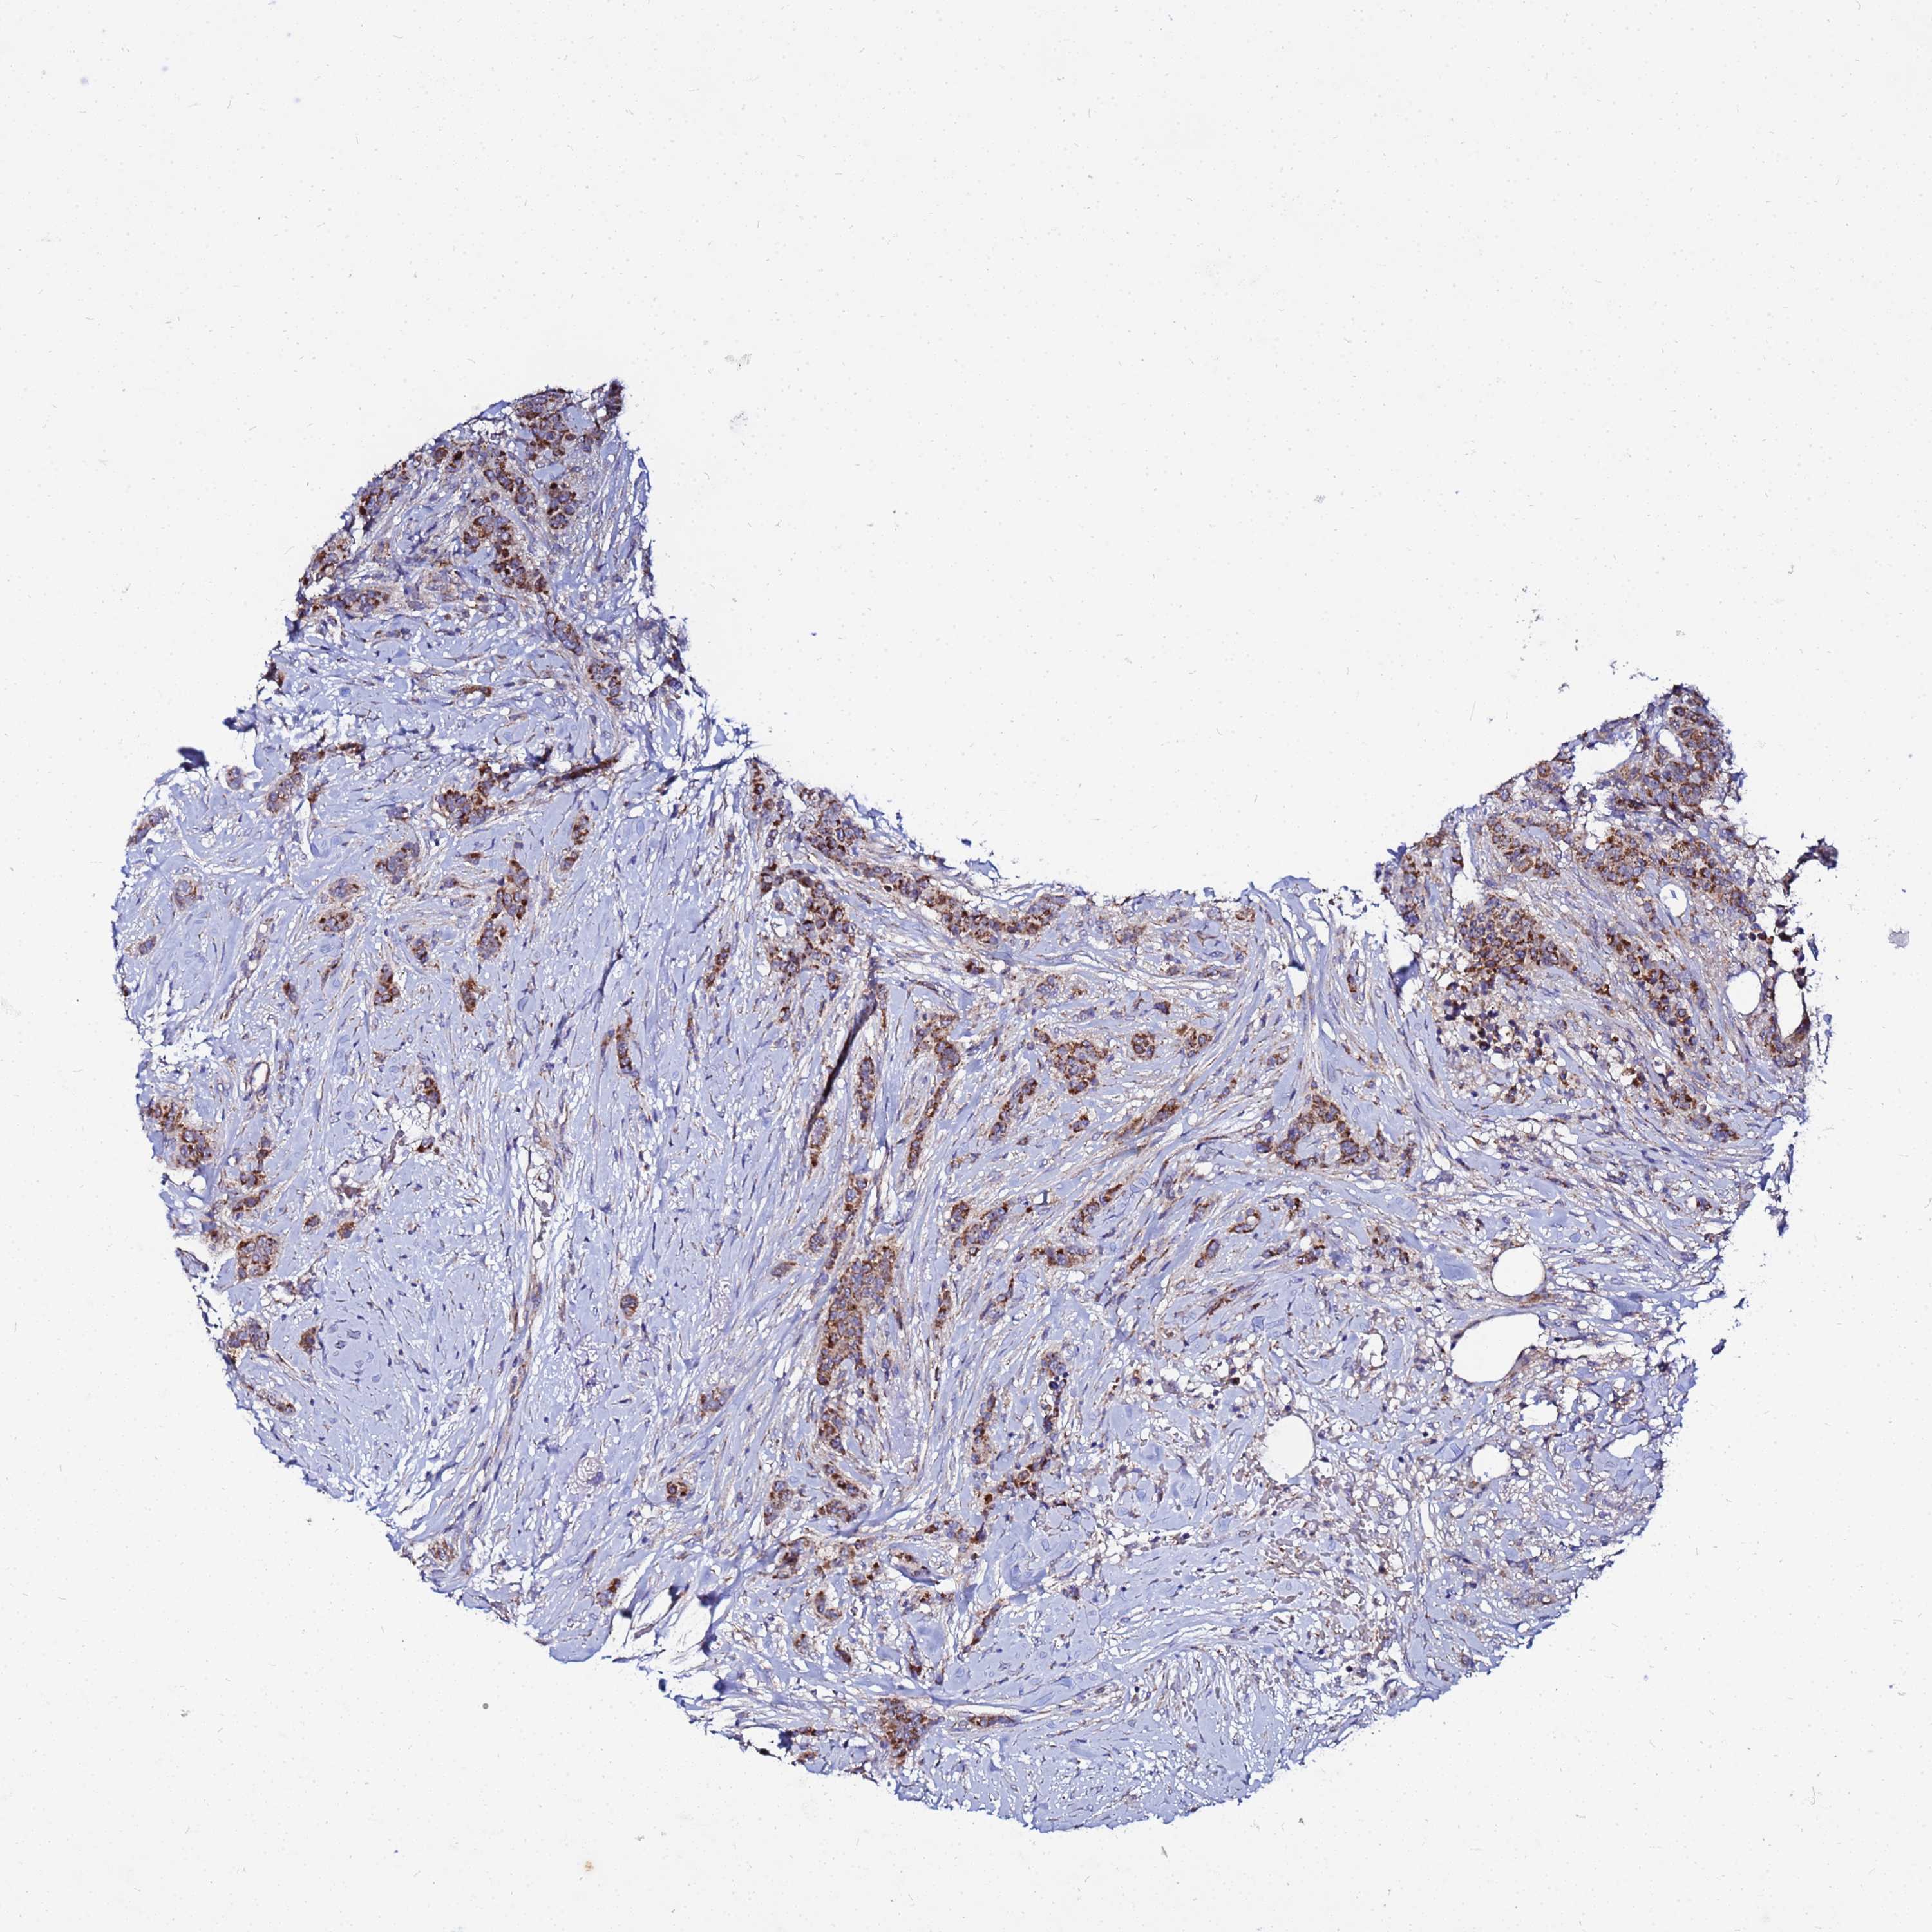

CANCER BREAST CANCER Show tissue menu

BRCA TCGA BRCA VALIDATION PROTEIN EXPRESSION